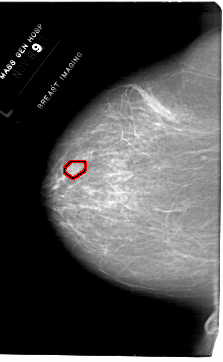

A_1768_1.LEFT_MLO

LEFT_MLO LINES 6301 PIXELS_PER_LINE 4216 BITS_PER_PIXEL 12 RESOLUTION 43.5 OVERLAY

FILE: A_1768_1.LEFT_MLO.OVERLAY

TOTAL_ABNORMALITIES 1

ABNORMALITY 1

LESION_TYPE MASS SHAPE OVAL MARGINS OBSCURED

ASSESSMENT 4

SUBTLETY 2

PATHOLOGY BENIGN

TOTAL_OUTLINES 1

BOUNDARY